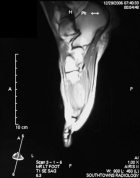

R.T. - 15 year old female noticed left dorsal foot mass two months ago; it is slightly tender to touch and bothers her with full plantar flexion, she also noticed some discoloration of the skin in the area

Zoom image: Radiological image Radiological image.